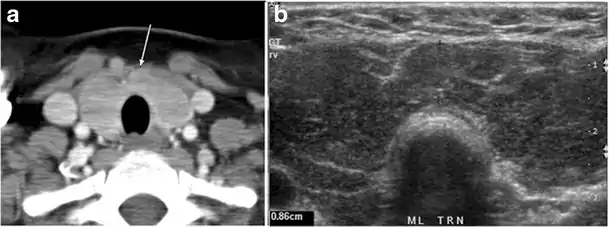

Fig. 3. An incidental PTC in a 62-year-old male patient with lymphoma. a, b Enhanced axial CT scan and fused PET/CT scan of the neck demonstrate a well-defined, hypodense right thyroid nodule (white arrow) with high FDG uptake. The FDG-avid uptake in the left side (circle) is related to patient's known lymphoma, which resolved after treatment. c, d Transverse greyscale and sagittal colour Doppler ultrasound of the neck demonstrate a right thyroid irregular hypoechoic lesion with some micro-calcifications (white arrows) and increased vascularity.[1]